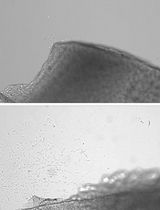

Tumorigenicity refers to the ability of cultured cells to develop viable tumors in immune-deficient animals. The goal of this protocol is to illustrate tumorigenicity assay by subcutaneous tumor-cell-transplantation in nude mice. Target cells are transplanted to 6-week-old nude mice subcutaneously and the tumor growth is monitored over a period of observation or treatment. When tumor grows to a pre-determined size or by the end of the limited period, the nude mice will be euthanatized and the xenograft will be removed for further examination.

With high incidence and mortality, tumor is one of the leading causes of death and is a major public health problem. Extensive studies are conducted every year to explore tumor pathogenesis and anti-tumor therapy. In the process of cancer research, tumorigenicity assay in nude mice is a widely used experiment to monitor tumor growth in vivo (Giovanella et al., 1974). The most commonly used animal system for tumorigenicity assay is athymic nude mouse (Petricciani et al., 1973) where malignant cells can be transplanted either subcutaneously or subrenal-capsularly (van Meir, 1997). For cells with relatively low ability of tumorigenicity, take rate can be improved by irradiation (30-60 Gy) or implantation in Matrigel (Pretlow et al., 1991). Tumorigenicity assay provides a means of generating human cell derived tumor tissues for measurement of tumor cell malignancy and evaluation for anti-tumor drug efficacy.